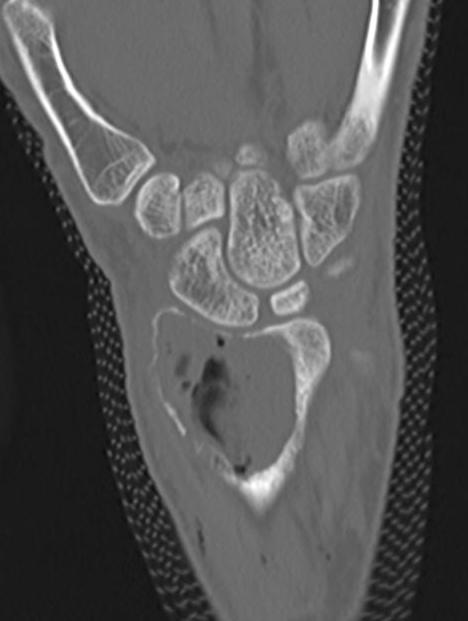

Distal Radius

Abuhejleh et al Eur J Orthop Traumatol Surg 2020

- 57 patients with GCT's of distal radius

- 29% (10/34) recurrence with intra-lesional treatement but no complications

- 4% (1/23) recurrence with wide resection / arthrodesis but 30% complication rate

- increased risk recurrence for Grade 3

- wide resection / arthrodesis should be reserved for grade 3

Koucheki et al Eur J Orthop Traumatol Surg 2023

- systematic review of 13 studies and 373 patients

- increased local recurrence with intralesional versus en-bloc resection

- especially Grade 3

- increased complications and poorer function with en-bloc resection

Distal radius GCT treated with en bloc resection and allograft reconstruction, followed by late wrist subluxation